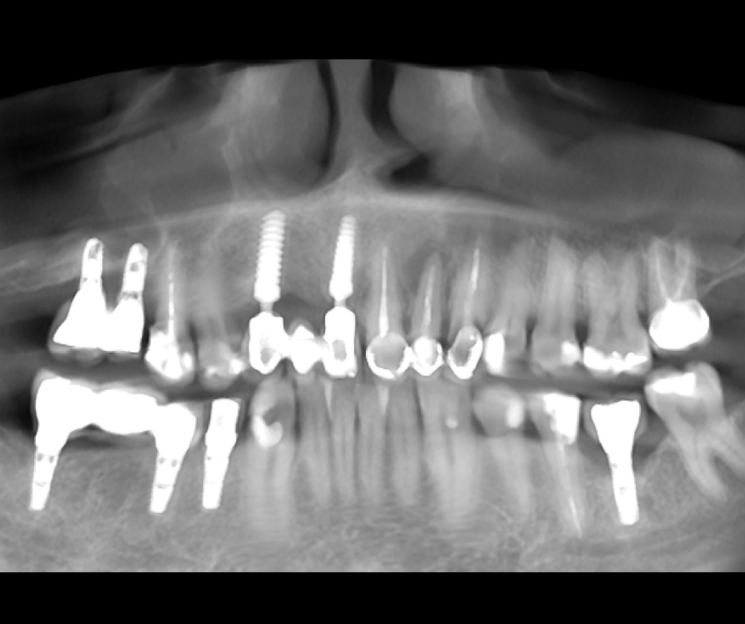

Paciente con infecciones de origen dental que comprometían severamente el hueso alveolar en la zona anterior superior. Se realizó la extracción de los dientes 21, 22 y 23, y se optó por una rehabilitación inmediata mediante implantes córticobasales.

Esta combinación permitió anclar los implantes en hueso cortical, que mantiene su estabilidad incluso en presencia de procesos infecciosos en el hueso alveolar. El resultado: rehabilitación funcional y estética el mismo día de la cirugía.